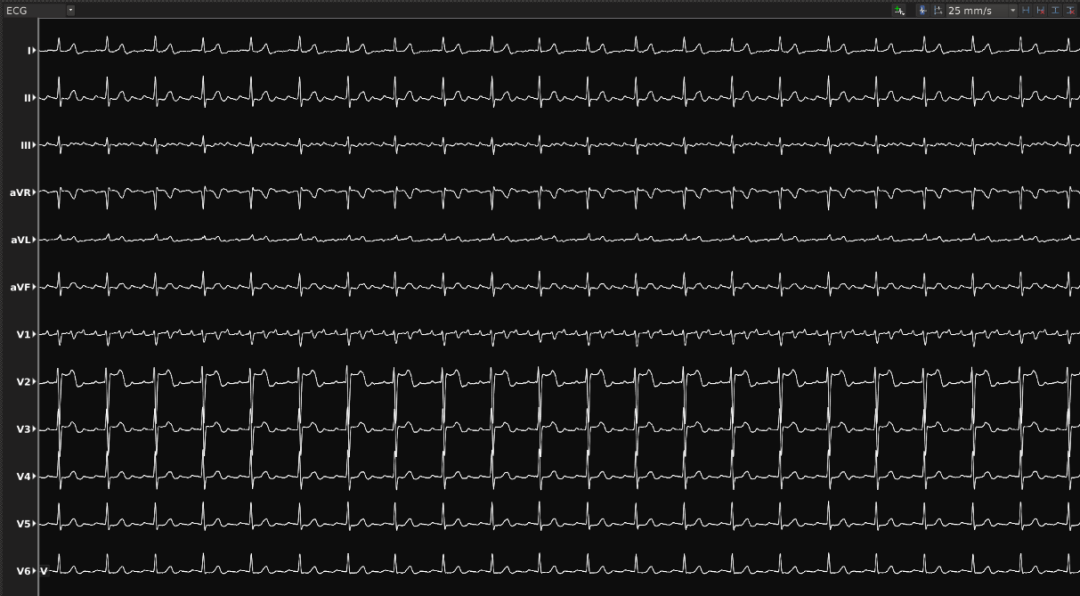

一位63岁的男性患者,二十多年前因“室上性心动过速”进行射频消融术,4年前进行肝脏移植。最近心悸持续多天不见缓解。于是该患者慕名至昆明医科大学第一附属医院就诊,后确诊为心房扑动。2022年5月25日,华宝桐主任团队对其实施房扑射频消融手术,这也是云南首例基于DIRECTSENSE™局部阻抗监测技术完成的房扑射频消融手术。

患者至手术室时心率为147次每分钟,常规消毒铺巾后,放置冠状窦十级导管,心室四极导管和Orion标测导管。在波士顿科学Rhythmia连续自动标测系统的指导下,利用Orion高密度标测导管快速标测右房。耗时7分43秒,获取有效标测点9611个(Projection Distance=2mm)。激动标测提示:冠状窦口最早激动,CL未标满,且最早点激动时间晚于CS5-6的A波,提示该房速可能来源于左房。遂穿刺房间隔至左房。利用Orion高密度标测导管快速标测左房。耗时9分钟39秒,获取有效标测点22410个(Projection Distance=2mm)。激动标测提示:左房游离壁有条阻滞线,左房后壁偏下位置有块疤痕区,房速机制绕左房后壁疤痕和右下肺静脉的逆钟向大折返。

ECG